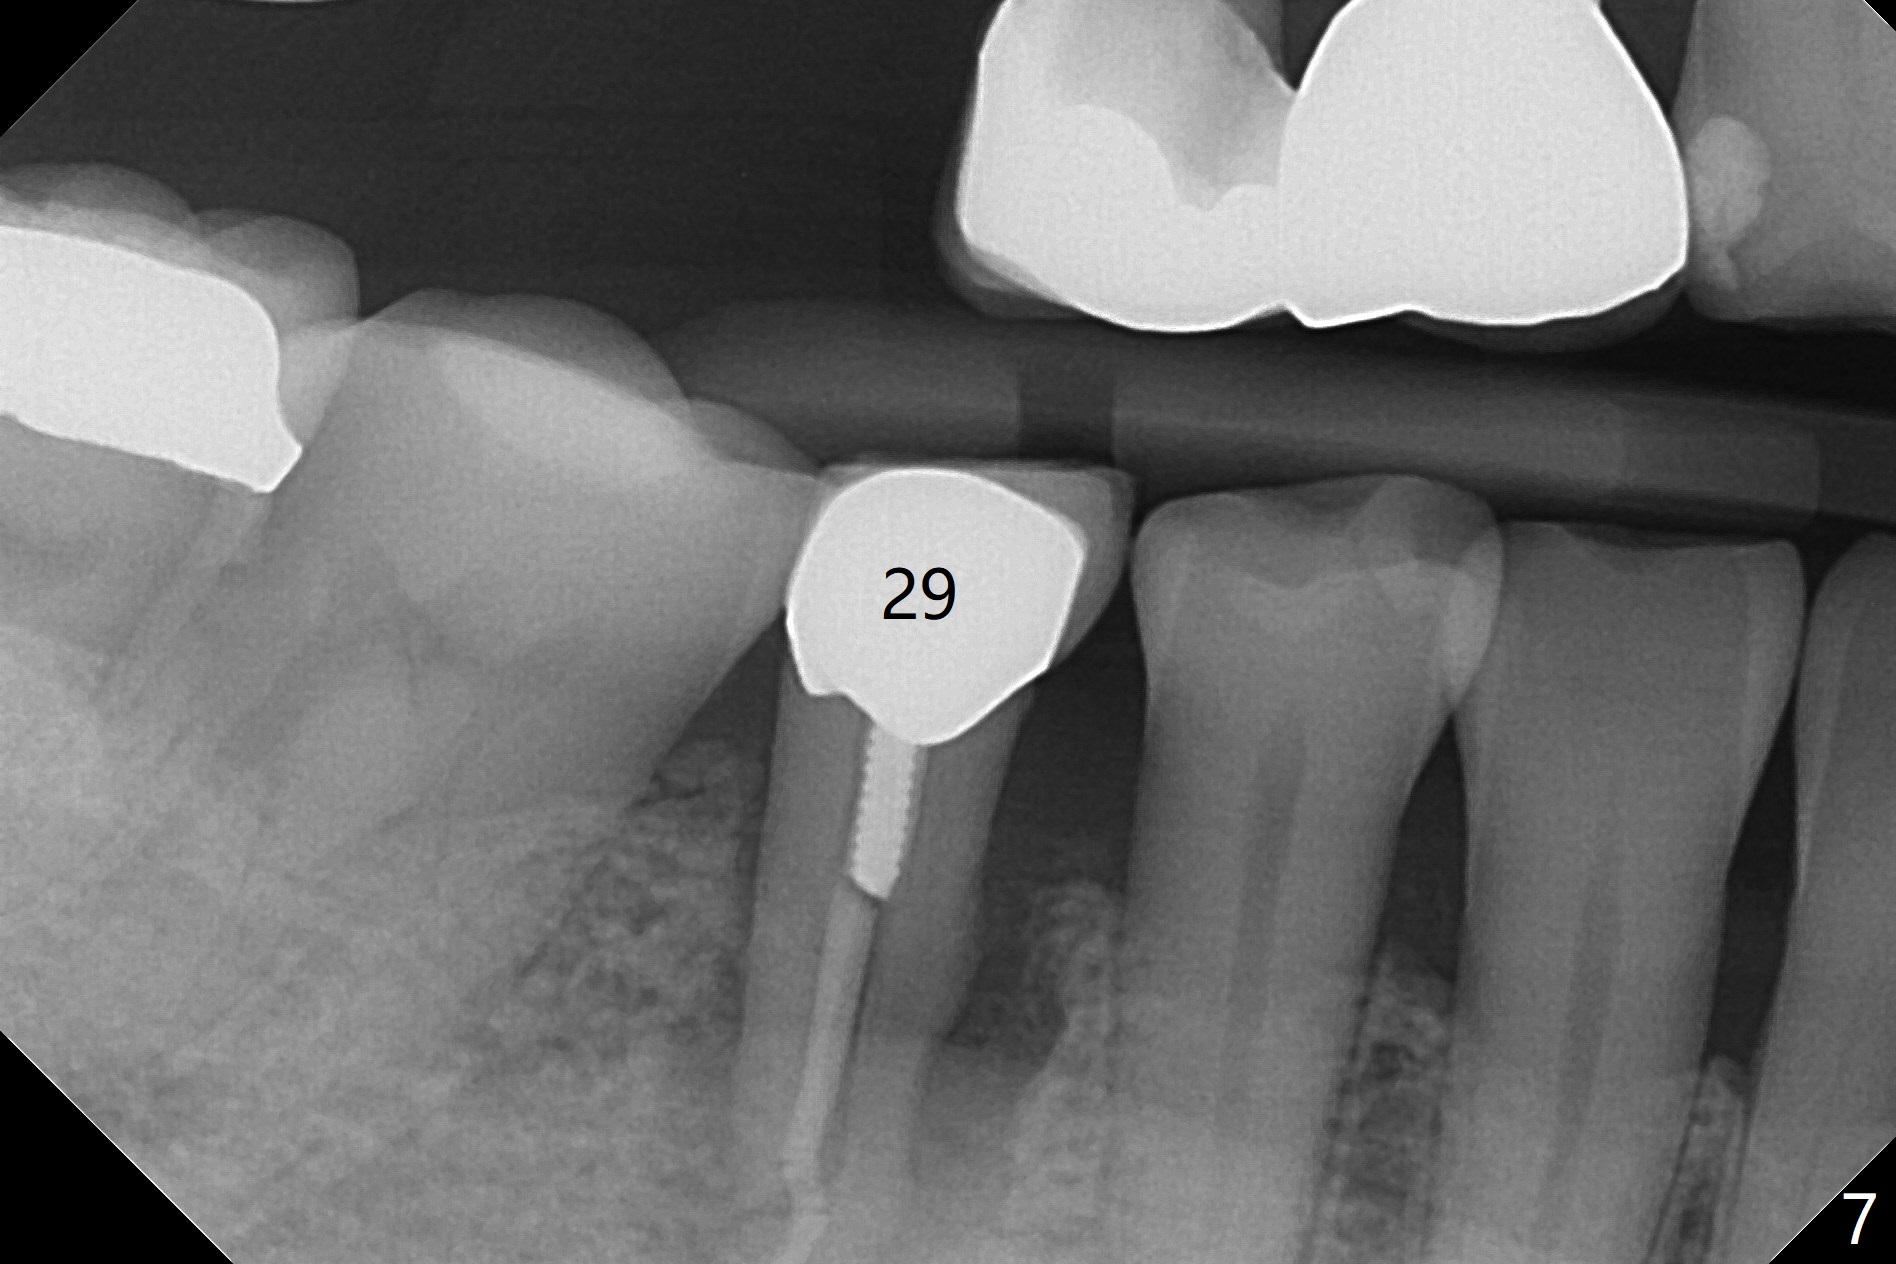

Osteotomy at the sites of #2 and 3 goes on as planned. Sinus lift using DIO 2.8 mm round bur with 6 and 7 mm stoppers (respectively) is carried on without certainty, because it is difficult to feel the stop through the osteotomy. The crest may be uneven or soft. It appears that the soft tissue landmark as a stop may be easier to identify. In fact a 3 mm IBS Magic Expander (an osteotome) was used for sinus lift at #3. The 2 implants are placed with 20 and 30 Ncm (Fig.1,2). Healing abutments are inserted. At 2-week follow-up, the patient reports "pain a few days earlier, took a pill of antibiotic, pain gone. UR metal is sharp". She does not take antibiotic regularly. Exam reveals that there is heavy plaque around #2,3 healing abutments. The buccal edge of #2 abutment is trimmed for comfort. Nearly 1 month postop, #3 healing abutment dislodges with buccal gingival erythema and edema with purulent discharge (Fig.3). Healing screw is placed at #3 with Amoxicillin and Chlorhexidine prescribed. One week later, the implant at #3 turns when the healing screw is retightened (Fig.4). After debridement, Vanilla graft is placed. There is no infection at #2 or 3 four months postop (Fig.5,6); the lingual gingiva is erythematous and edematous at #29 with mobility II (Fig.7 (vertical root fracture)). Uncover is conducted at the site of #3; there is no infection superficial 7.5 months postop (Fig.8). There is a large buccal defect upon incision with dark hemorrhage. In fact the bone density is low crestally (Fig.8 *). Bone graft is placed for the 2nd time. Eleven months later (1.5 years post implant placement), the bone regrows crestal (Fig.9 *). The crown at #3 is loose 1 year 5 months post cementation (Fig.10). After proximal trimming (Fig.11 *), the abutment at #3 is seated completely. After lab repair, crown oral cement, crown/abutment removal for excess cement removal, the crown/abutment cannot be torqued >25 Ncm (Fig.12, 30 Ncm). PA shows incomplete seating (Fig.12 <). Then the crown is sectioned so that the abutment has more freedom to be seated completely with pressure against the gingiva (the patient feels pain, Fig.13). Torque is 30 Ncm. After crown cementation, the abutment will not be removed for cement removal.